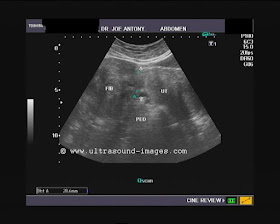

This middle aged lady has a very small uterus (called hypoplasia of the uterus). Such a uterus is incompatible with the ability to conceive and have a child. The ultrasound video clip below shows a sagittal (midline) section through the uterus. It was obtained via the transvaginal route. The vagina itself was sufficiently large enough to insert the transvaginal probe.

The inner lining of the uterine cavity- the endometrium appears markedly thinned, and again this is incompatible with conceiving a child.

The ultrasound video clip below is a transverse section through the uterus of the same patient: